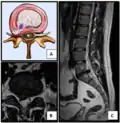

- Click images to see larger versions

-

Lumbar disc lesions, classification -

Normal situation and spinal disc herniation in cervical vertebrae -

Illustration depicting herniated disc and spinal nerve compression -

Nucleus herniating through tear in annulus (with MRI)[9] -

Illustration showing disc degeneration, prolapse, extrusion and sequestration